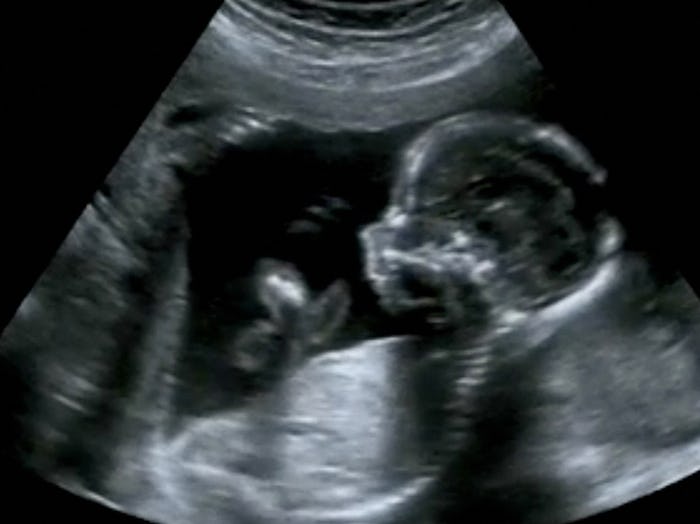

Smiling

OMG. For real? Yes! Your baby is practicing everything in there, and that includes facial expressions. 4-D ultrasounds have even caught some babies in the smiling act. But their emotions run the full gamut, so while they can put on a happy face, they can also cry. Yes, quivering lower lip and all.